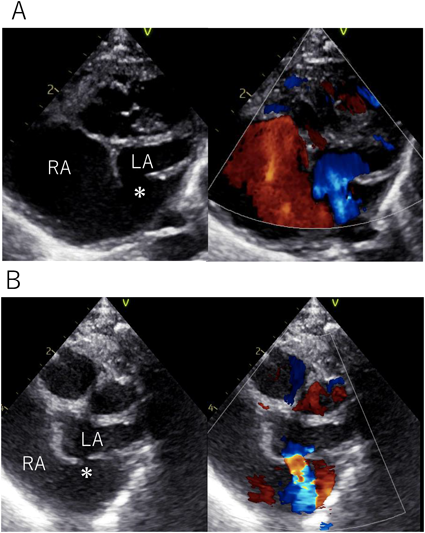

致命的となりうるunroofed coronary sinusの自然閉鎖を認めた僧帽弁閉鎖合併単心室例Spontaneous Closure of a Potentially Fatal Unroofed Coronary Sinus in a Case of Mitral Valve Atresia with a Single Ventricle